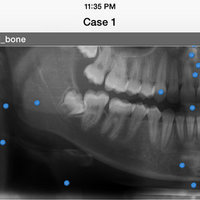

iPanoramic

Panoramic radiographs provide a quick overview of the patient’s teeth, jaws, and bone. This is useful for diagnoses and treatment planning.

The app provides dental students and dental hygiene an easy and fun way to master different anatomical landmarks. Dental practitioners can use the app to refresh their knowledge about panoramic radiographs. The app can be used a quick reference when needed. It's fully interactive and allows knowledge assessment through a quiz mode.